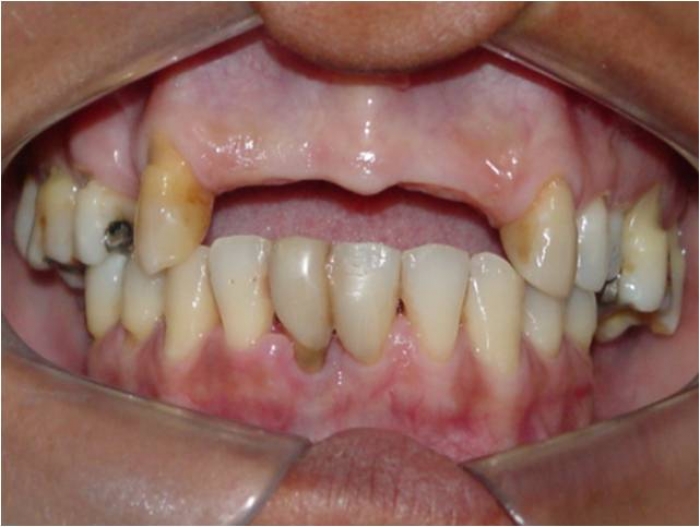

Sorriso inicial